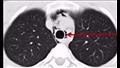

في واقعة صادمة، أُصيب شاب من مدينة شينزين بالصين باسترواح الصدر، أو ما يُعرف بـ "الرئة المنهارة" ، بينما كان يصرخ بصوت عالٍ خلال حفل موسيقي لفرقة غنائية مفضلة لديه.

واسترواح الصدر هو تجمع غير طبيعي للهواء في الحيز الجنبي بين الرئة وجدار الصدر، يمكن أن يحدث بسبب إصابة حادة أو اختراق في الصدر أو تمزق بسبب الضغط المفاجئ أو الشديد.